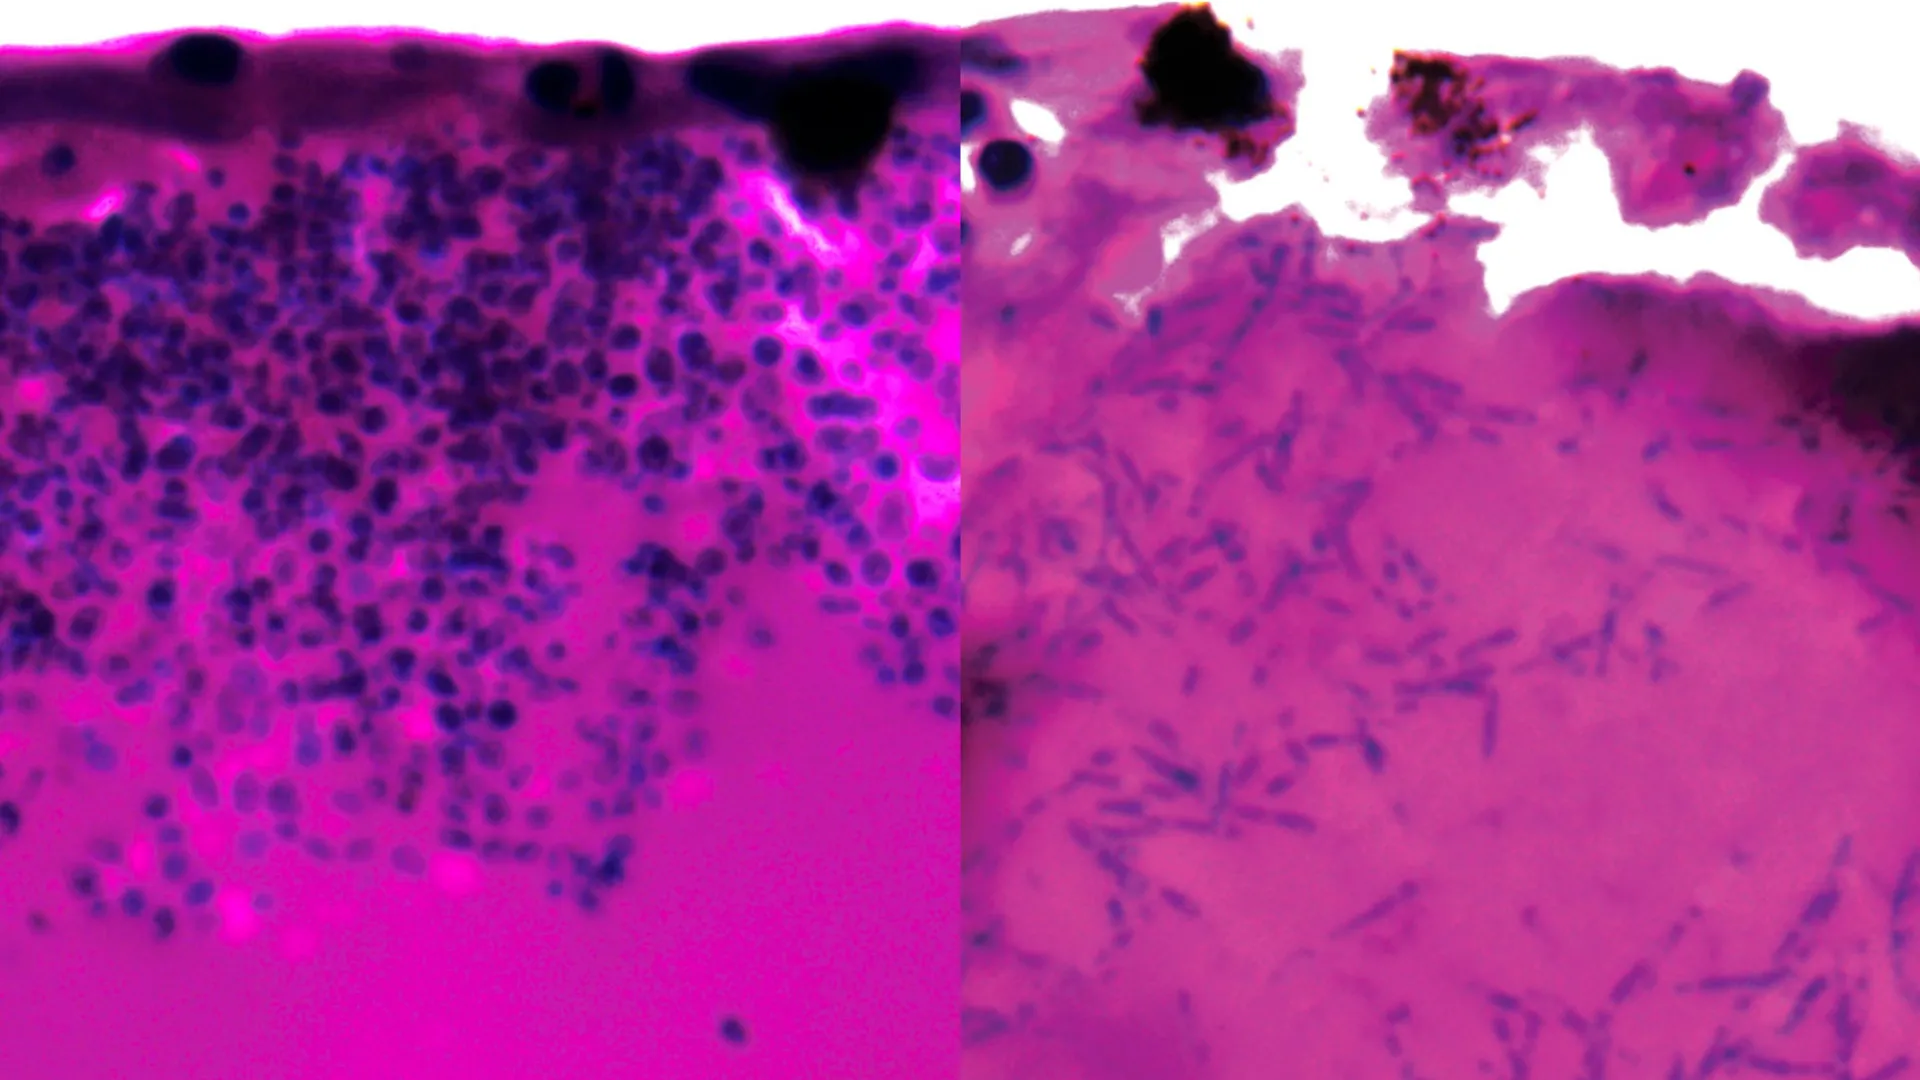

Scientists have identified a genetic mechanism that could point to new ways of treating a rare but deadly fungal infection that has forced multiple hospital intensive care units to shut down. The finding offers early hope against a pathogen that…

Scientists find a weak spot in deadly fungus that shut down hospital intensive care units